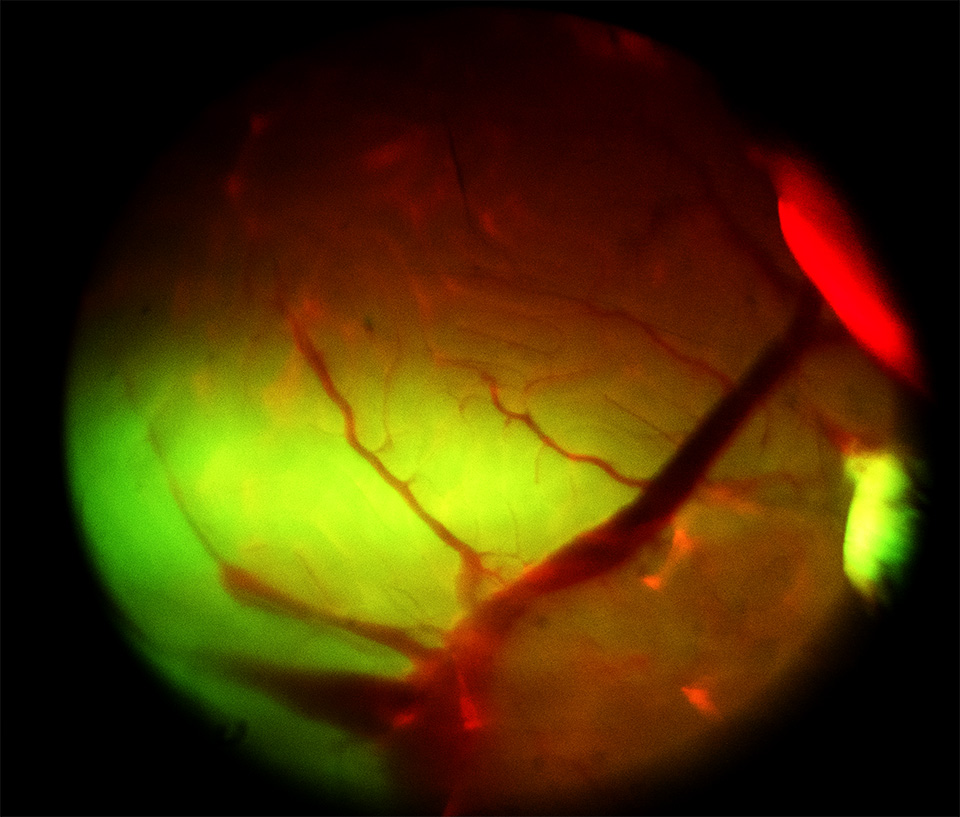

Specs: 3D scan for organ (exvivo / in vivo).

image00 ex vivo

image00 image00 image00 image00 image00 image00 image00 image00 image00 image00 image00 image00 in vivo